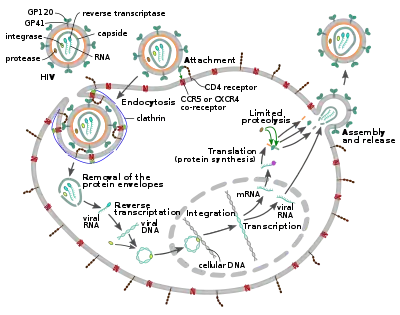

The HIV replication cycle

The HIV virion enters macrophages and CD4+ T cells by the adsorption of glycoproteins on its surface to receptors on the target cell followed by fusion of the viral envelope with the target cell membrane and the release of the HIV capsid into the cell.[58][59]

Entry to the cell begins through interaction of the trimeric envelope complex (gp160 spike) on the HIV viral envelope and both CD4 and a chemokine co-receptor (generally either CCR5 or CXCR4, but others are known to interact) on the target cell surface.[58][59] Gp120 binds to integrin α4β7 activating LFA-1, the central integrin involved in the establishment of virological synapses, which facilitate efficient cell-to-cell spreading of HIV-1.[60] The gp160 spike contains binding domains for both CD4 and chemokine receptors.[58][59]

The first step in fusion involves the high-affinity attachment of the CD4 binding domains of gp120 to CD4. Once gp120 is bound with the CD4 protein, the envelope complex undergoes a structural change, exposing the chemokine receptor binding domains of gp120 and allowing them to interact with the target chemokine receptor.[58][59] This allows for a more stable two-pronged attachment, which allows the N-terminal fusion peptide gp41 to penetrate the cell membrane.[58][59] Repeat sequences in gp41, HR1, and HR2 then interact, causing the collapse of the extracellular portion of gp41 into a hairpin shape. This loop structure brings the virus and cell membranes close together, allowing fusion of the membranes and subsequent entry of the viral capsid.[58][59]

After HIV has bound to the target cell, the HIV RNA and various enzymes, including reverse transcriptase, integrase, ribonuclease, and protease, are injected into the cell.[58] During the microtubule-based transport to the nucleus, the viral single-strand RNA genome is transcribed into double-strand DNA, which is then integrated into a host chromosome.

Replication and transcription

Shortly after the viral capsid enters the cell, an enzyme called reverse transcriptase liberates the positive-sense single-stranded RNA genome from the attached viral proteins and copies it into a complementary DNA (cDNA) molecule.[68] The process of reverse transcription is extremely error-prone, and the resulting mutations may cause drug resistance or allow the virus to evade the body's immune system. The reverse transcriptase also has ribonuclease activity that degrades the viral RNA during the synthesis of cDNA, as well as DNA-dependent DNA polymerase activity that creates a sense DNA from the antisense cDNA.[69] Together, the cDNA and its complement form a double-stranded viral DNA that is then transported into the cell nucleus. The integration of the viral DNA into the host cell's genome is carried out by another viral enzyme called integrase.[68]

The integrated viral DNA may then lie dormant, in the latent stage of HIV infection.[68] To actively produce the virus, certain cellular transcription factors need to be present, the most important of which is NF-κB (nuclear factor kappa B), which is upregulated when T cells become activated.[70] This means that those cells most likely to be targeted, entered and subsequently killed by HIV are those actively fighting infection.

During viral replication, the integrated DNA provirus is transcribed into RNA. The full-length genomic RNAs (gRNA) can be packaged into new viral particles in a pseudodiploid form. The selectivity in the packaging is explained by the structural properties of the dimeric conformer of the gRNA. The gRNA dimer is characterized by a tandem three-way junction within the gRNA monomer, in which the SD and AUG hairpins, responsible for splicing and translation respectively, are sequestered and the DIS (dimerization initiation signal) hairpin is exposed. The formation of the gRNA dimer is mediated by a 'kissing' interaction between the DIS hairpin loops of the gRNA monomers. At the same time, certain guanosine residues in the gRNA are made available for binding of the nucleocapsid (NC) protein leading to the subsequent virion assembly.[71] The labile gRNA dimer has been also reported to achieve a more stable conformation following the NC binding, in which both the DIS and the U5:AUG regions of the gRNA participate in extensive base pairing.[72]

RNA can also be processed to produce mature messenger RNAs (mRNAs). In most cases, this processing involves RNA splicing to produce mRNAs that are shorter than the full-length genome. Which part of the RNA is removed during RNA splicing determines which of the HIV protein-coding sequences is translated.[73]

Mature HIV mRNAs are exported from the nucleus into the cytoplasm, where they are translated to produce HIV proteins, including Rev. As the newly produced Rev protein is produced it moves to the nucleus, where it binds to full-length, unspliced copies of virus RNAs and allows them to leave the nucleus.[74] Some of these full-length RNAs function as mRNAs that are translated to produce the structural proteins Gag and Env. Gag proteins bind to copies of the virus RNA genome to package them into new virus particles.[75] HIV-1 and HIV-2 appear to package their RNA differently.[76][77] HIV-1 will bind to any appropriate RNA.[78] HIV-2 will preferentially bind to the mRNA that was used to create the Gag protein itself.[79]

Assembly and release

The final step of the viral cycle, assembly of new HIV-1 virions, begins at the plasma membrane of the host cell. The Env polyprotein (gp160) goes through the endoplasmic reticulum and is transported to the Golgi apparatus where it is cleaved by furin resulting in the two HIV envelope glycoproteins, gp41 and gp120.[87] These are transported to the plasma membrane of the host cell where gp41 anchors gp120 to the membrane of the infected cell. The Gag (p55) and Gag-Pol (p160) polyproteins also associate with the inner surface of the plasma membrane along with the HIV genomic RNA as the forming virion begins to bud from the host cell. The budded virion is still immature as the gag polyproteins still need to be cleaved into the actual matrix, capsid and nucleocapsid proteins. This cleavage is mediated by the packaged viral protease and can be inhibited by antiretroviral drugs of the protease inhibitor class. The various structural components then assemble to produce a mature HIV virion.[88] Only mature virions are then able to infect another cell.